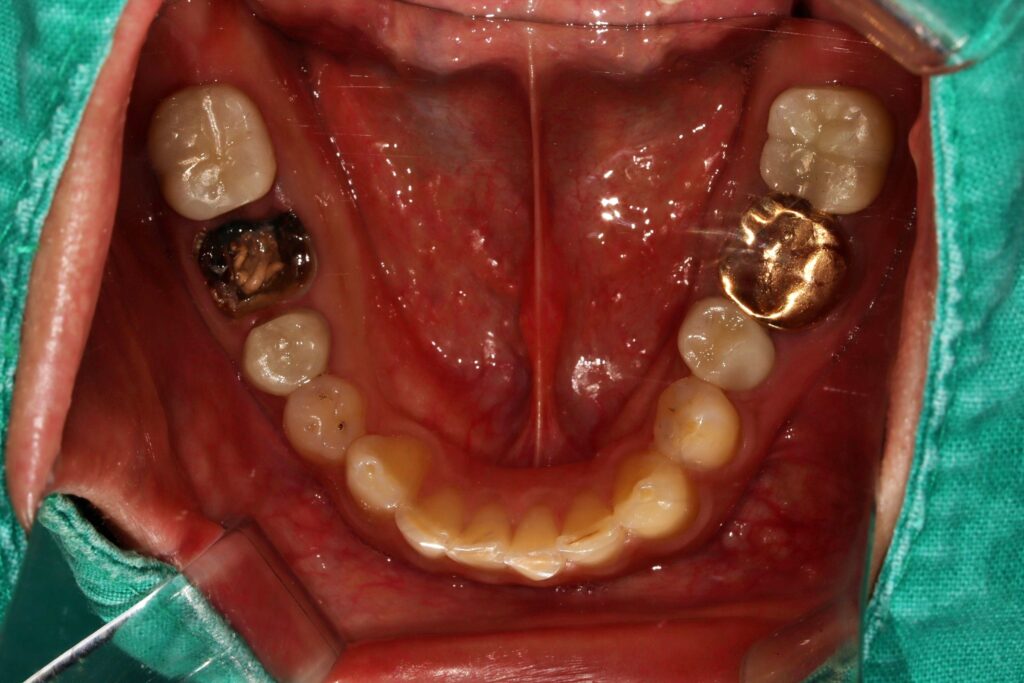

오른쪽 치아의 크라운 탈락으로 오신분인데요

자세히 보시면 아래 어금니가 살짝 보이실 거예요

원래는 금니가 있으셨는데

오래돼서 크라운이 빠져버렸다고 하셨어요

위에서 봤을 때 치아 내부가 까맣게 변해있죠

안에 분홍색은 옛날 치료했던 재료이구요

15년 정도 됐다고 하니..

저 분홍이도 그렇게나 오래되었겠죠